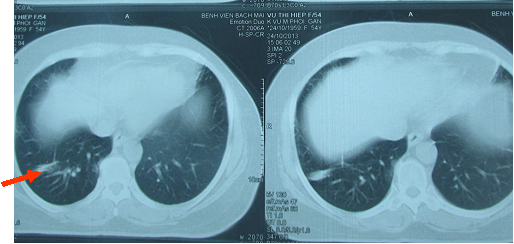

• CT scanner phổi, nốt di căn phổi phải kích thước (1,8x2)cm (hình 1).

Hình 1: Hình chụp CT lồng ngực cho thấy u phổi phải dạng di căn, kích thước (1,8x2)cm ngấm thuốc mạnh sau tiêm